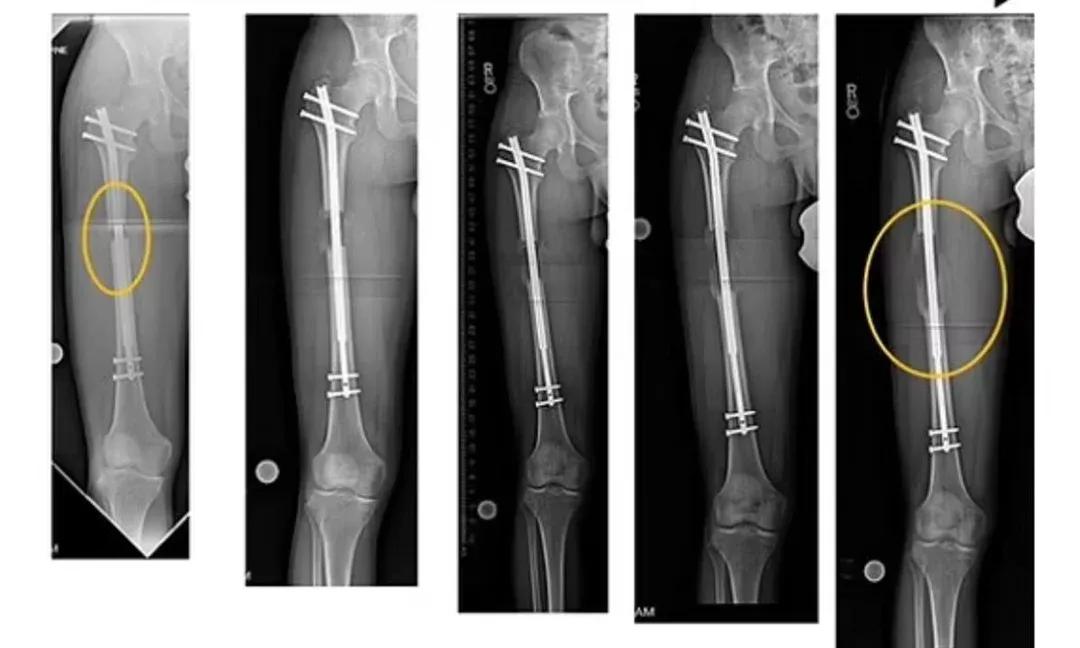

为了能让自己“长”得更高一些,莱昂一连做了3次“腿部延长”手术。

近日,莱昂的第3次手术,在土耳其顺利完成,这也让他的身高从172厘米,“长”到了现在的190厘米,整整“长”了18厘米。

其方法大致是:先将增高者的双腿通过手术截断,再用专业的仪器,朝相反的方向牵拉断骨两端。断骨在再生能力下,会慢慢地向外生长,大约每天可生长0.5至1毫米。直到两端的断骨,在慢慢生长中互相连接、愈合为止。